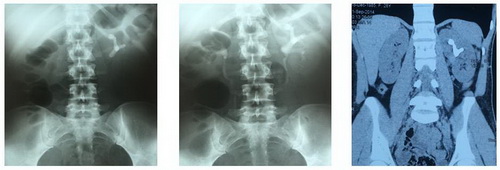

Рис. Обзорная рентгенография и мультиспиральная компьютерная томография.

Рис. Рентгенологические этапы операции.